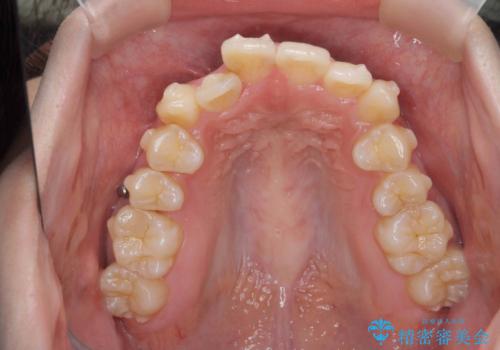

前歯のがたつきをマウスピース矯正できれいに!

- 目立つ前歯のがたつきを改善したい、と矯正治療を希望され来院されました。

今回の治療ではシミュレーションでしっかりと検討した結果、下顎は前歯を1本抜去し仕上げる治療計画としました。